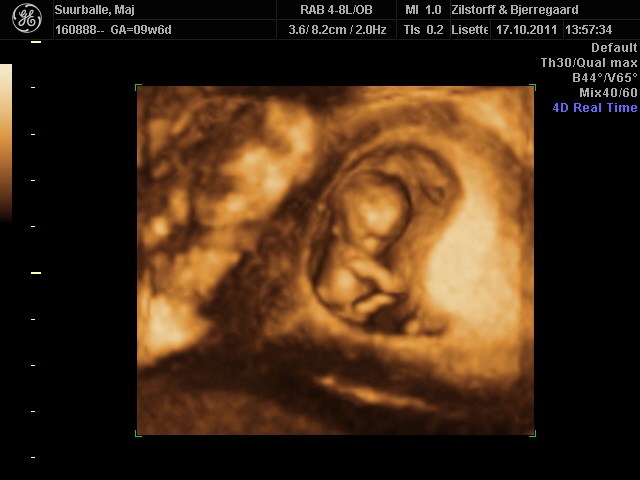

Troede ikke at den var så "levende" allerede.. Den lille fister på knap 3,4 cm sprællede helt vildt jo! Og tænk at den allerede har arme, ben, små øre, noget der ligner øjne, næse...... HELT vildt at opleve <3

Ja, det er det.. Og nu lærte jeg det lige lidt bedre tror jeg...: 4D bruger de til at se bevægelserne.

Og vi fik så både s/h, 3D og 4D